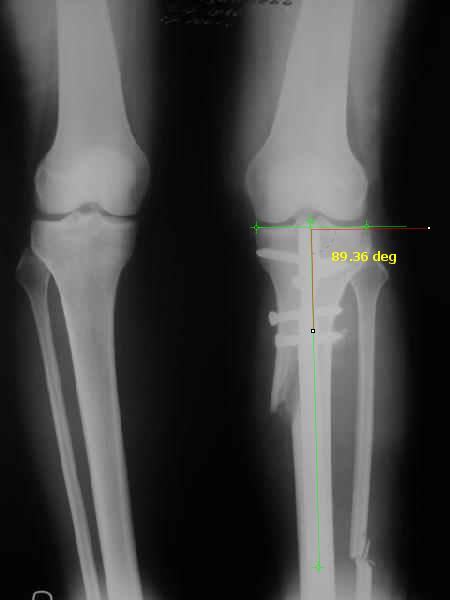

Отправитель: T. Derek V. Cooke 13 Сентябрь 2005, 23:51

|

Hello Alex:

Thanks for the clinical photo.

Your patient appears to have "Insquinting Knees"?

I am attaching a word doc with a 'print screen' of the program in use, showing the images being viewed and analysed

. On the right leg you can see some of the tools (from the tool bar above) applied to demonstrate a mild mech-axis varus of about 5 degrees.

On the left the bone landmarks used in the anlaysis are shown.

The data for the analysis are in the XLs sheet below, exported from the program automatically.

I have given a label of the abreviations and some normative values.

In essence she has a mild mech-axis varus of 7 degrees with some contribution from the femur (2) degrees and more from the tibia (6 degrees), none from the joint.

The analysis took about 6 mins.

Regards

Derek

TDVC> In essence she has a mild mech-axis varus of 7 degrees

TDVC> with some contribution from the femur (2) degrees and more from

TDVC> the tibia (6 degrees), none from the joint.

And what is conclusion? Should it be corrected, by what means, at what level, to what axis, with what lateral/medial translation?